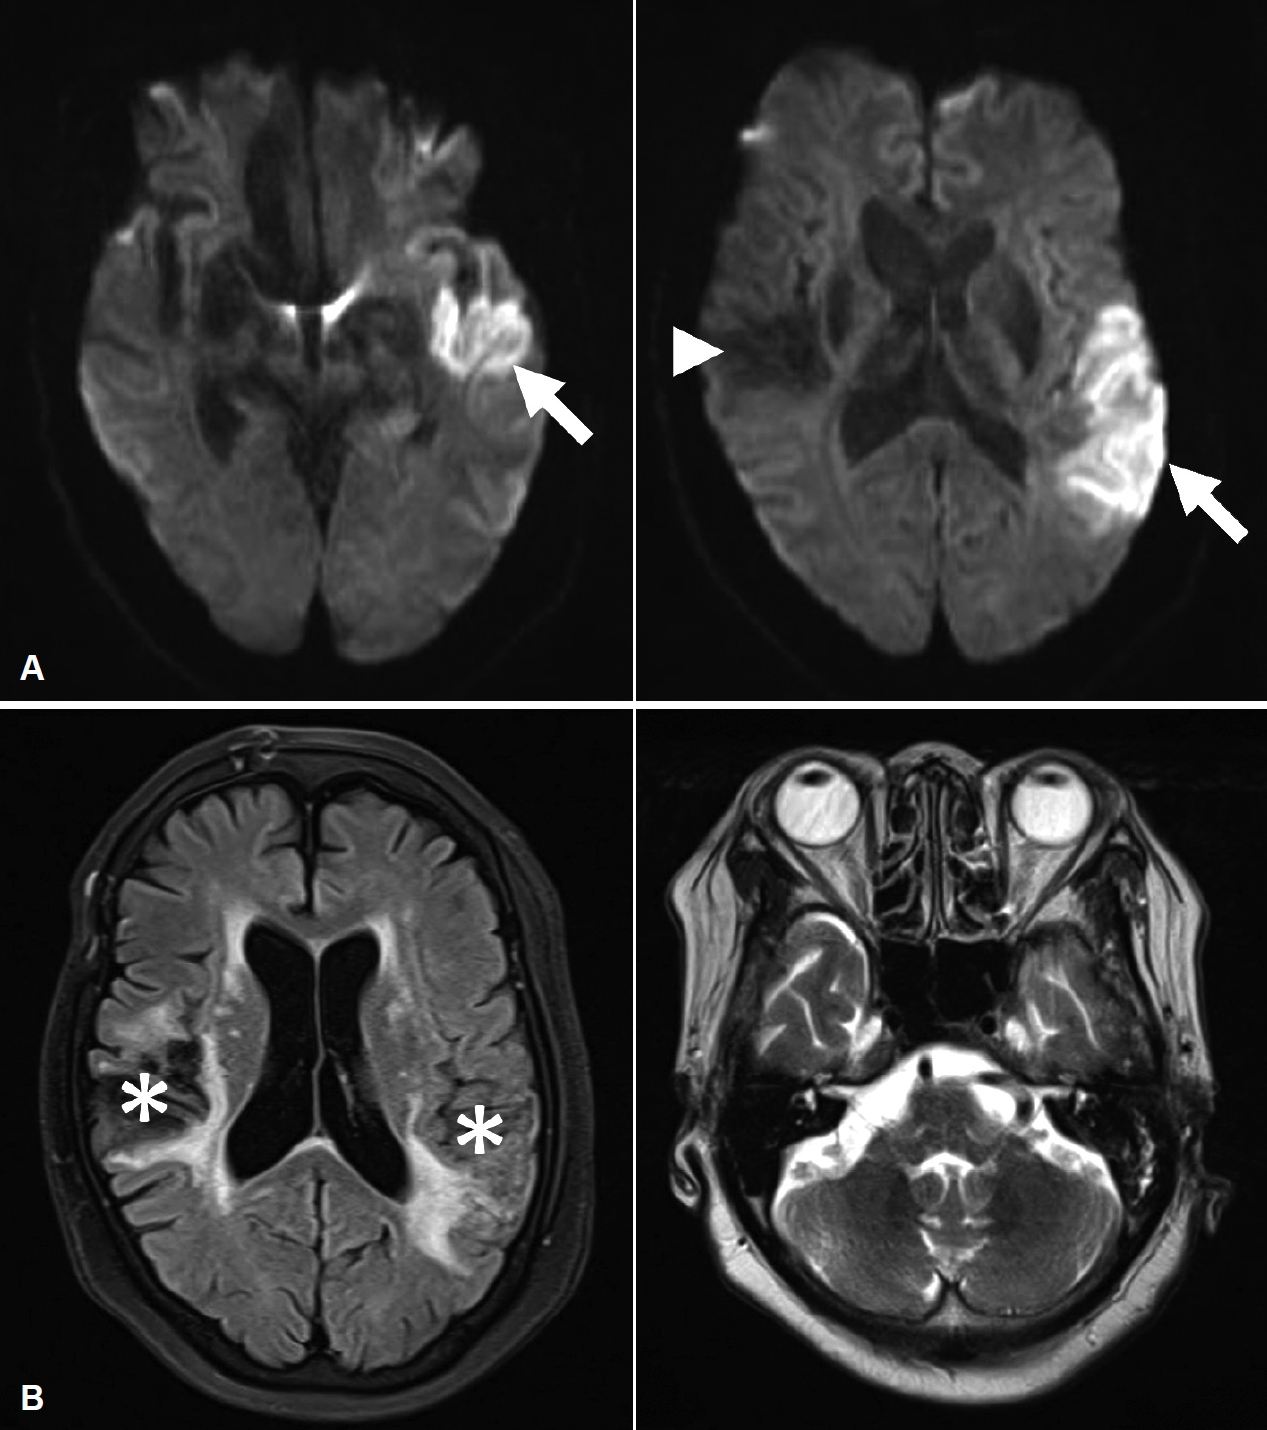

내원 당일 시행한 뇌자기공명영상에서 일차청각피질을 포함하는 좌측 측두엽에서 급성 뇌경색이 확인되었다(Fig. 1). 이후 입원하여 시행한 뇌혈관조영술에서는 좌측 중대뇌동맥의 폐색이 확인되었으나 조영술 도중에 저절로 재개통되었고, 이전에 시술받았던 우측 전교통동맥 동맥류 결찰술 부위는 온전하였으나 좌측 중대뇌동맥 이분지에서 새롭게 동맥류가 확인되었다(Fig. 2). 이에 환자는 신경외과로 입원하여 항응고요법 및 재교통 시술을 포함한 급성 뇌경색 치료를 진행하였고, 입원 후에도 13일째 지속되는 양측 청각장애에 대해 본과로 전과되었다.

Fig. 1.MRI. Diffusion-weighted images of initial MRI show patchy high signal intensity (arrows) in left parieto-temporal lobe, suggesting acute infarction. Old infarction with encephalomalacia (arrowhead) is also shown in right temporal lobe (A). T2-weighted images of MRI followed 3 months later shows encephalomalacia (asterisks) in both temporal lobes but does not find out any retrocochlear lesion (B). Fig. 2.Angiography. Lateral view shows that left middle cerebral artery (arrowhead) was occluded initially but recanalized spontaneously during angiography (A). Anteroposterior view confirms that left middle cerebral artery M2 aneurysm (black arrow) was successfully filled with coil (white arrow) (B). Fig. 3.Results of electrophysiologic auditory tests. (A) Click auditory brainstem response test (headphones, low pass filter=100 Hz, high pass filter=3000 Hz, averaging=1024). Interwave intervals of 1–3 waves=2.17 msec, 3–5 waves=1.79 msec and 1–5 waves=3.96 msec in right ear; 1–3 waves=2.46 msec, 3–5 waves=1.75 msec and 1–5 waves=4.21 msec in left ear. (B) Auditory steady-state response test. Fig. 4.Pure-tone audiogram. Initial audiogram (A) and audiogram of 1.5 months after the onset (B). They show flat sensorineural hearing loss of mild degree in both ears. Table 1.Summary of central auditory nervous system disorders Table 2.Summary of reported cases of central deafness